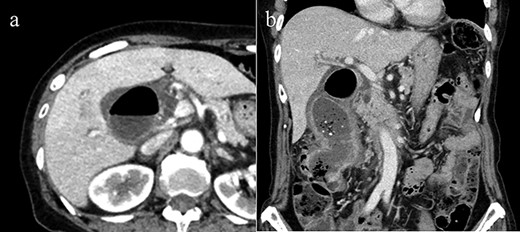

Abdominal ultrasound showed gallbladder wall thickness and many gallstones. Multidetector computed tomography (MDCT) with intravenous contrast material revealed gallbladder distension, a thick-walled gallbladder and inflammation in pericholecystic soft tissues (Fig. 1). Air in the gallbladder and a fistulous connection between the gallbladder and transverse colon were also detected. The diameter of the fistula was ~2 cm. However, tumorous lesions inside the gallbladder were not confirmed.

(a) Axial CT image reveals pneumobilia and wall thickness of the gallbladder, but did not show fistulous connection with the colon clearly. (b) Coronal view of CT demonstrates CCF. No CT imaging angle could clearly show the tumorous lesion.